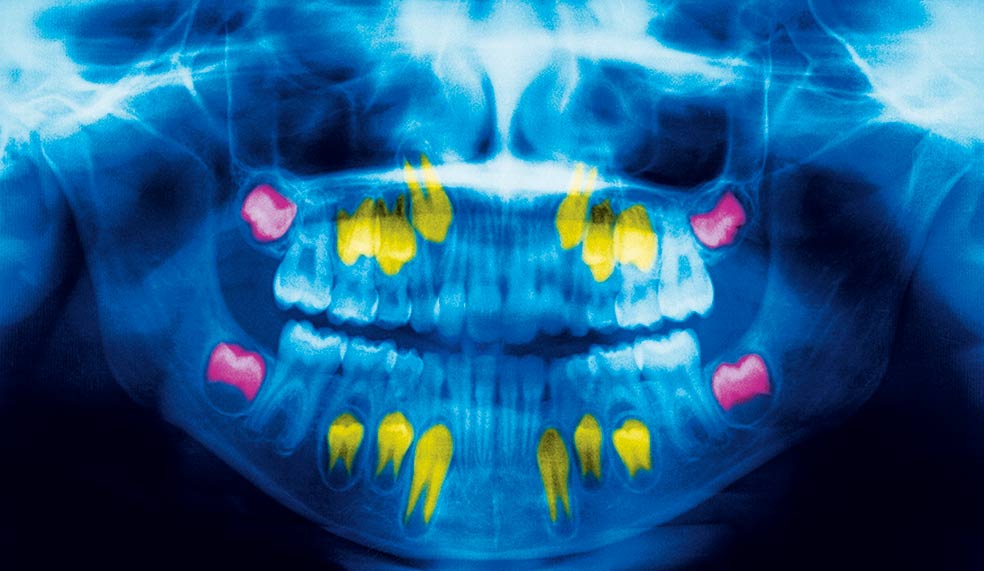

La formación de los dientes comienza antes de nacer, entre la sexta y la octava semana de desarrollo. Capas de esmalte van acumulándose, dejando marcas cada 6 o 12 días, que forman una serie de anillos concéntricos similares a los del árbol al crecer. Esos aros funcionan como biomarcadores que podrían permitir conocer la existencia de traumas o adversidades en la infancia o en fase fetal: pobreza familiar, un suceso traumático, un desastre natural...

Todo deja huella en las capas de esmalte. Esto permitiría anticipar la aparición de enfermedades. Por ejemplo, hay un aro negro en las capas interiores del esmalte que tenemos todos. Se conoce como 'línea neonatal' y corresponde con nuestro primer episodio estresante: el parto. Se sabe que episodios traumáticos y estrés crónico pueden dejar marcas físicas en el cuerpo y el cerebro.

Si la violencia u otro trauma o dificultad (léase guerra o desastre natural) ha aparecido en la infancia, durante el desarrollo de la estructura cerebral, es fácil que los niños crezcan con problemas cognitivos o emocionales o una mayor propensión a padecer cáncer o enfermedades coronarias. Para la investigadora Erin Dunn resulta importante contar con un indicador objetivo que muestre problemas psiquiátricos padecidos en la infancia. Y lo ha encontrado en los dientes que decenas de voluntarios le envían. Son analizados por rayos X y tomografía axial antes de cortarlos en finas 'rebanadas' que permiten analizar los anillos de esmalte. Y buscar huellas de eventos traumáticos.